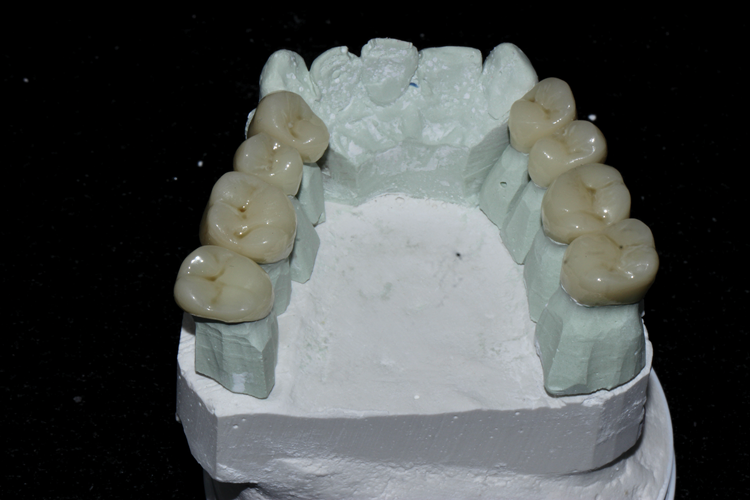

(8.) View of the maxillary and mandibular posterior full-coverage composite crowns, which were designed and milled with an increased vertical dimension position. This position was determined after intraoral testing was conducted with a leaf gauge instrument.

Figure 8

(9.) View of the maxillary and mandibular posterior full-coverage composite crowns, which were designed and milled with an increased vertical dimension position. This position was determined after intraoral testing was conducted with a leaf gauge instrument.

Figure 9